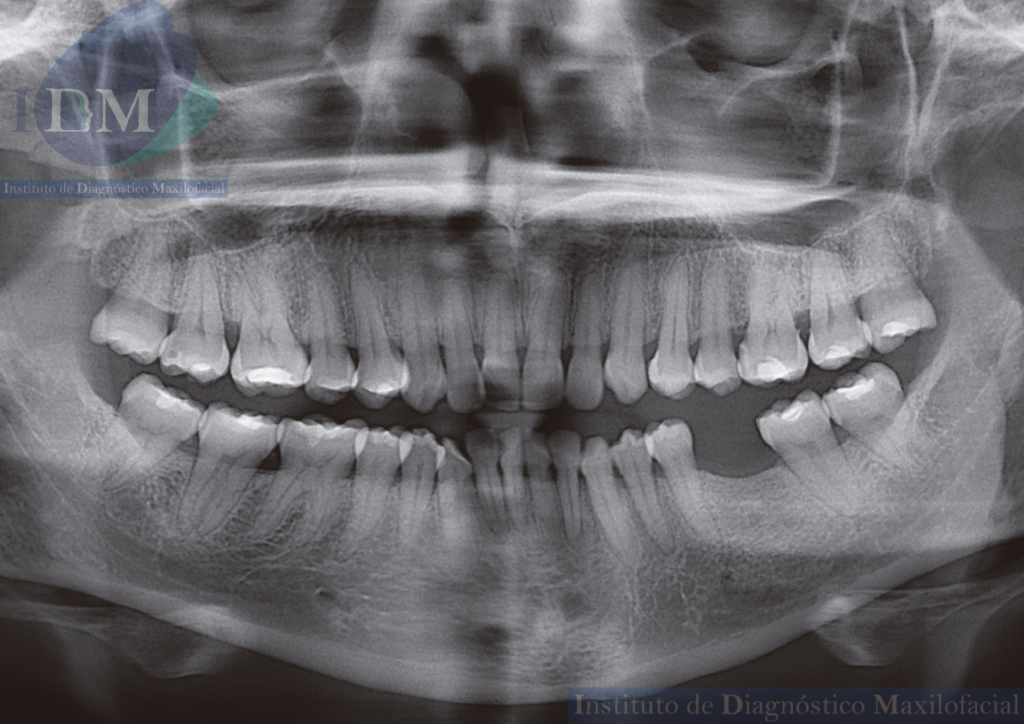

En la radiografía panorámica (Figura 1), se aprecia neumatización alveolar de senos maxilares, múltiples piezas con material restaurador y bifurcación del conducto dentario inferior del lado izquierdo.

Radiografia Panorámica